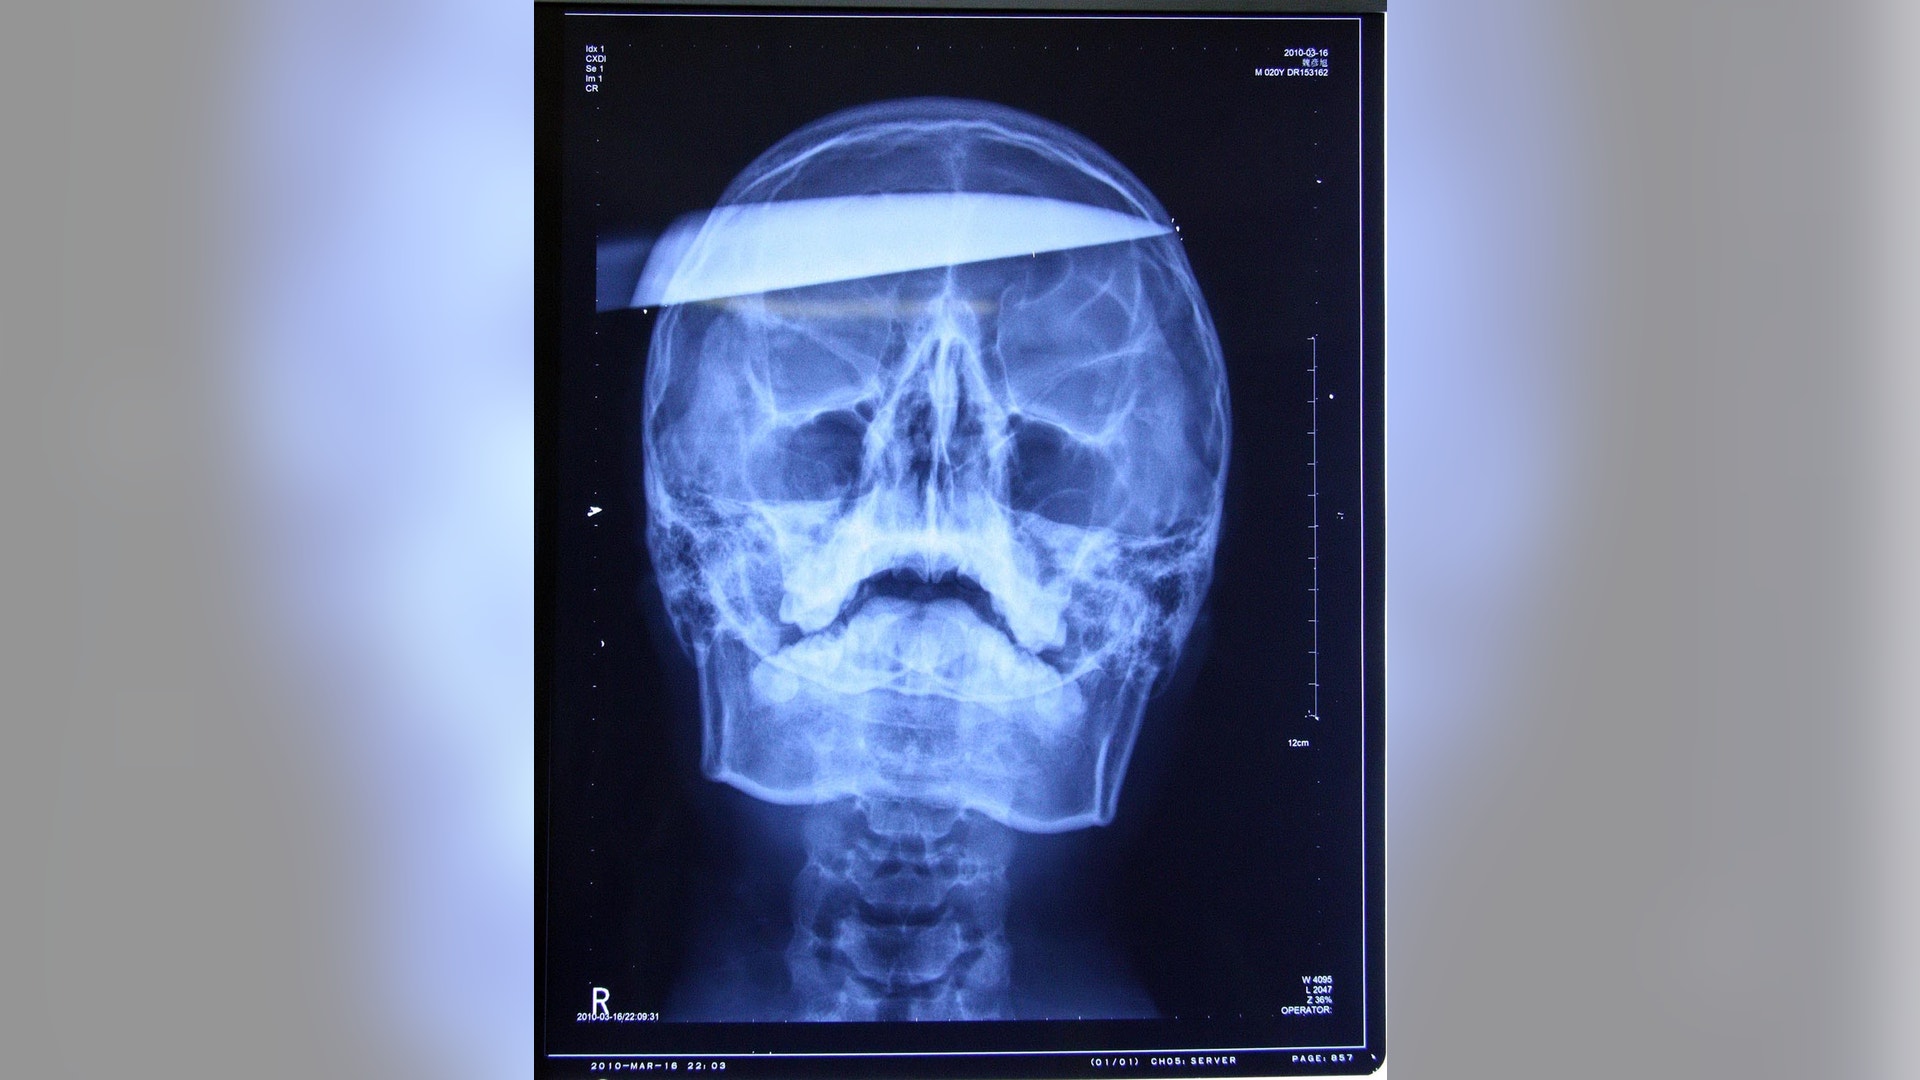

Xiao Wei, 16, who was attacked in a dispute over the video game he was playing, was able to walk into the emergency room entrance of Jillin University with the 10-inch knife still lodged in his head. An operation to remove the blade took more than two hours. X-rays and CAT scans revealed that no main arteries or nerves were damaged.read more![Phone in Stomach]()